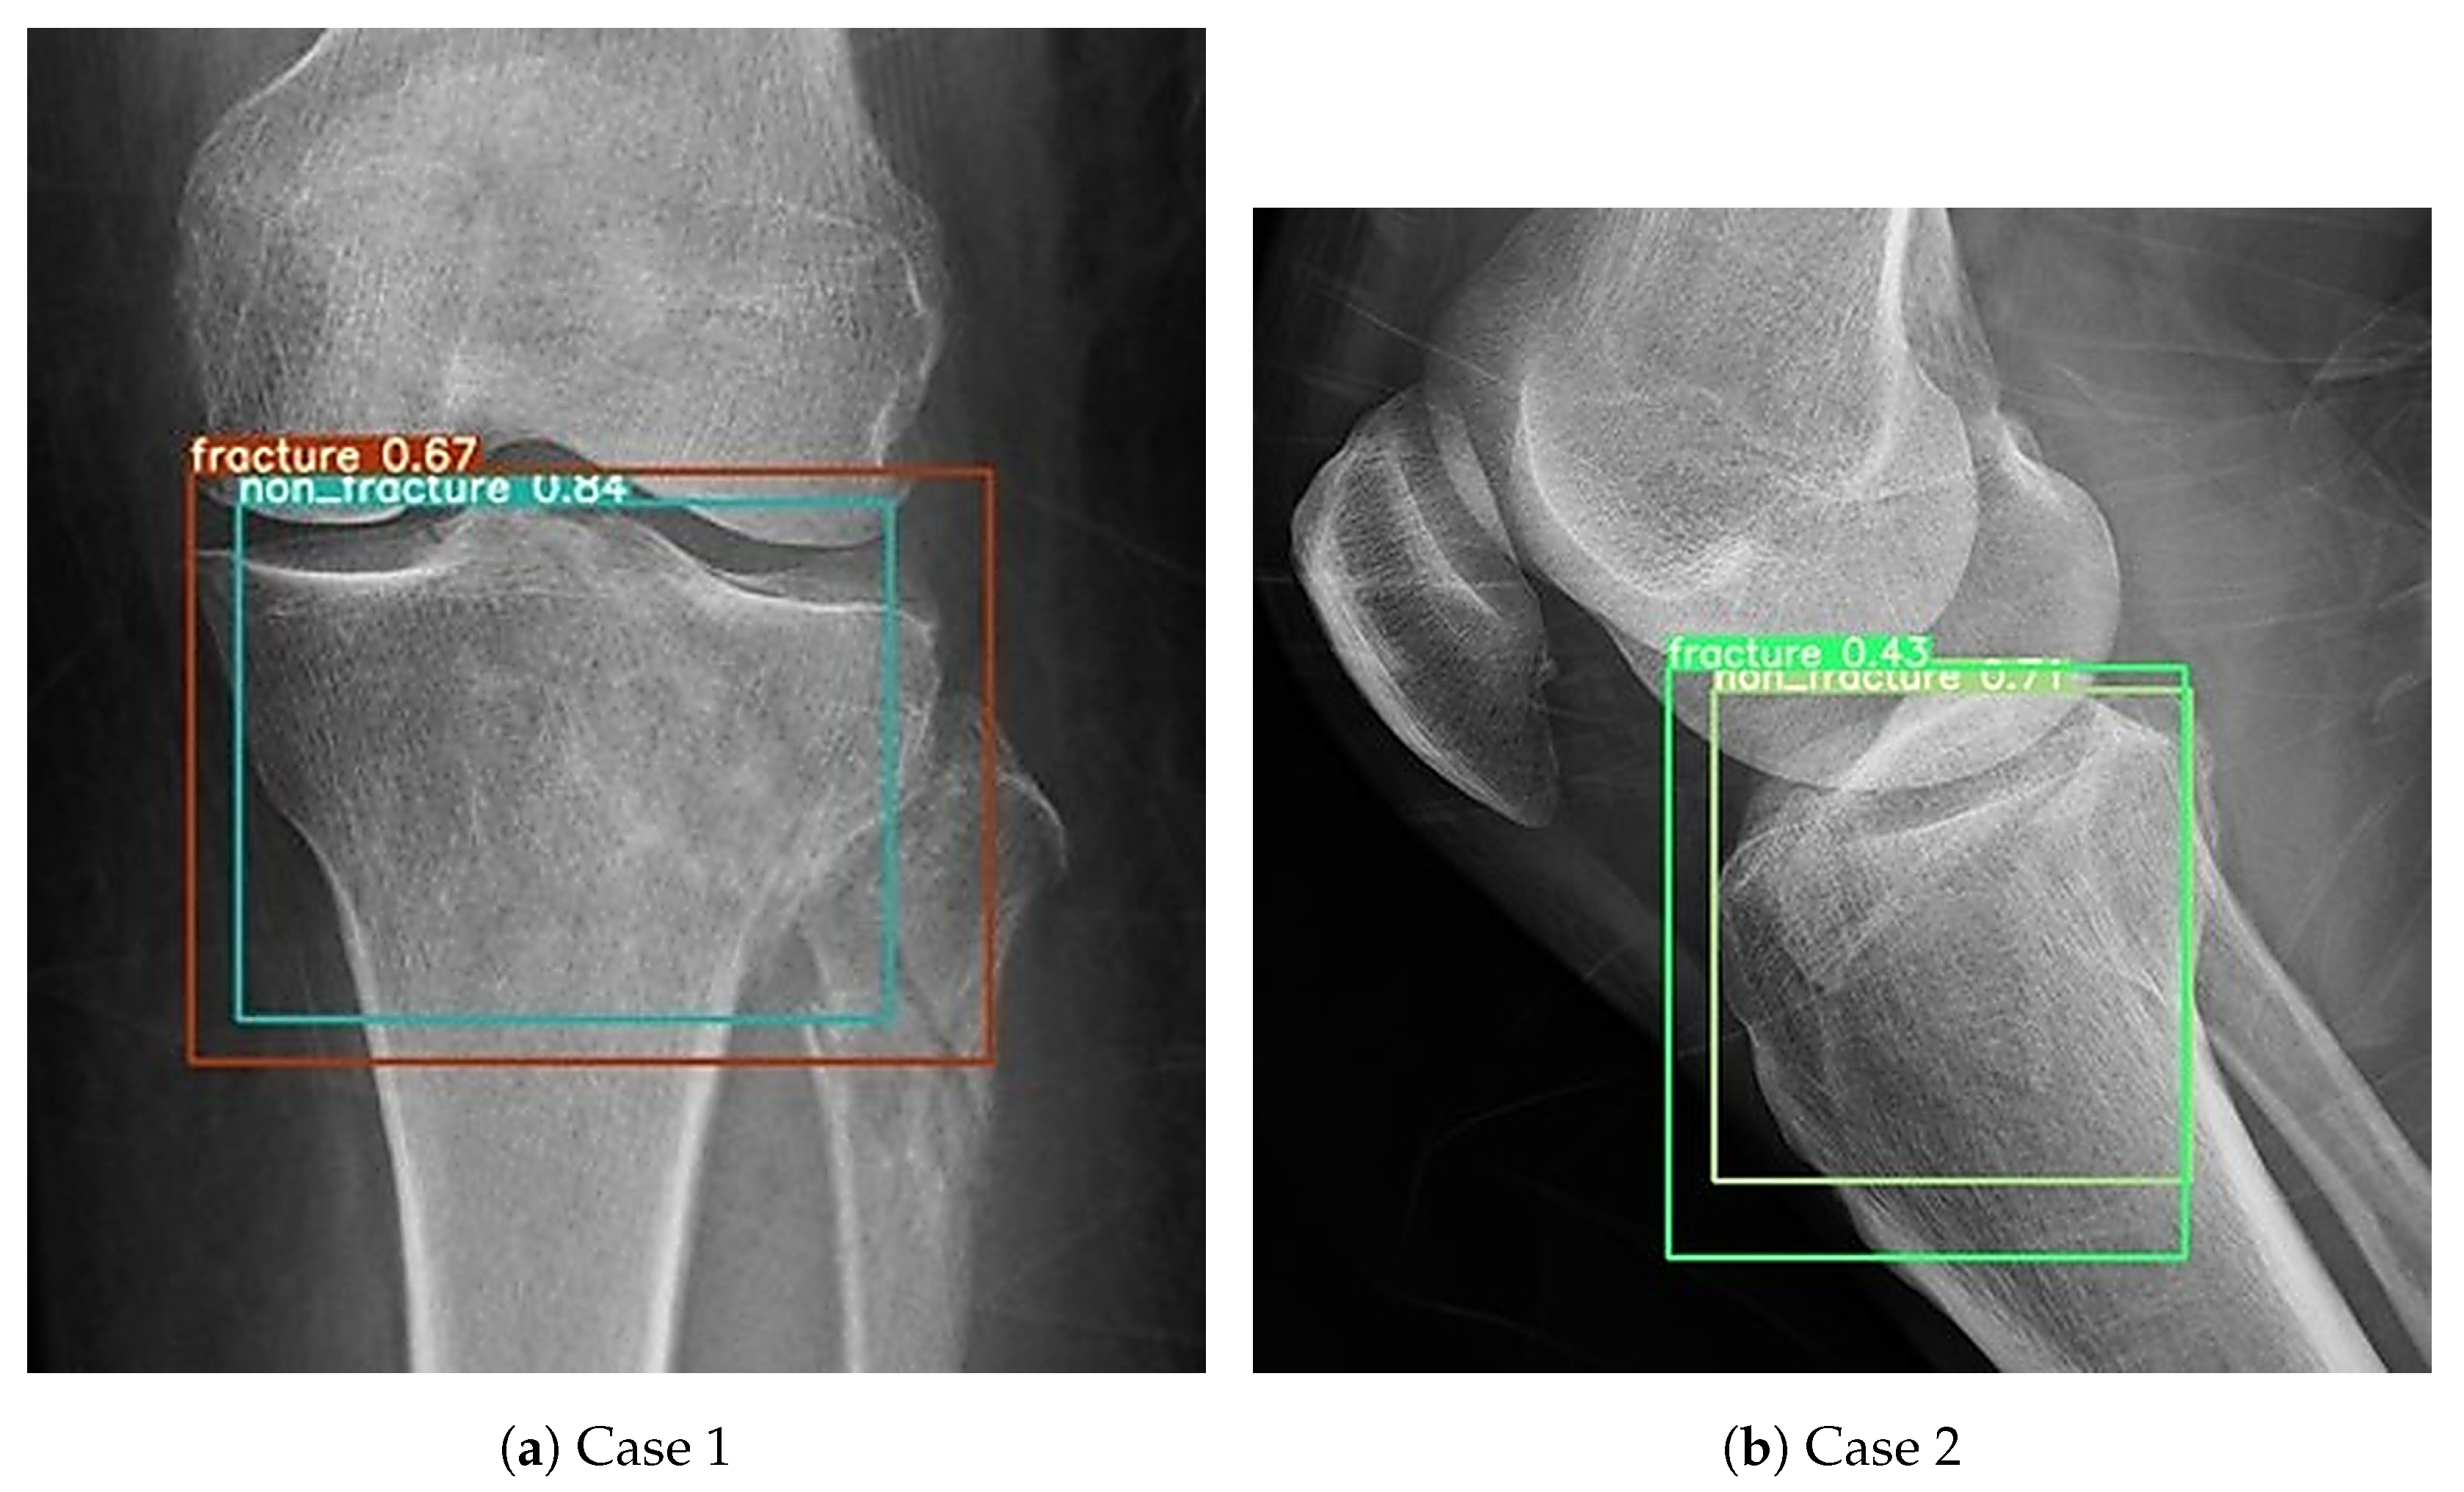

3.3. Data Annotation